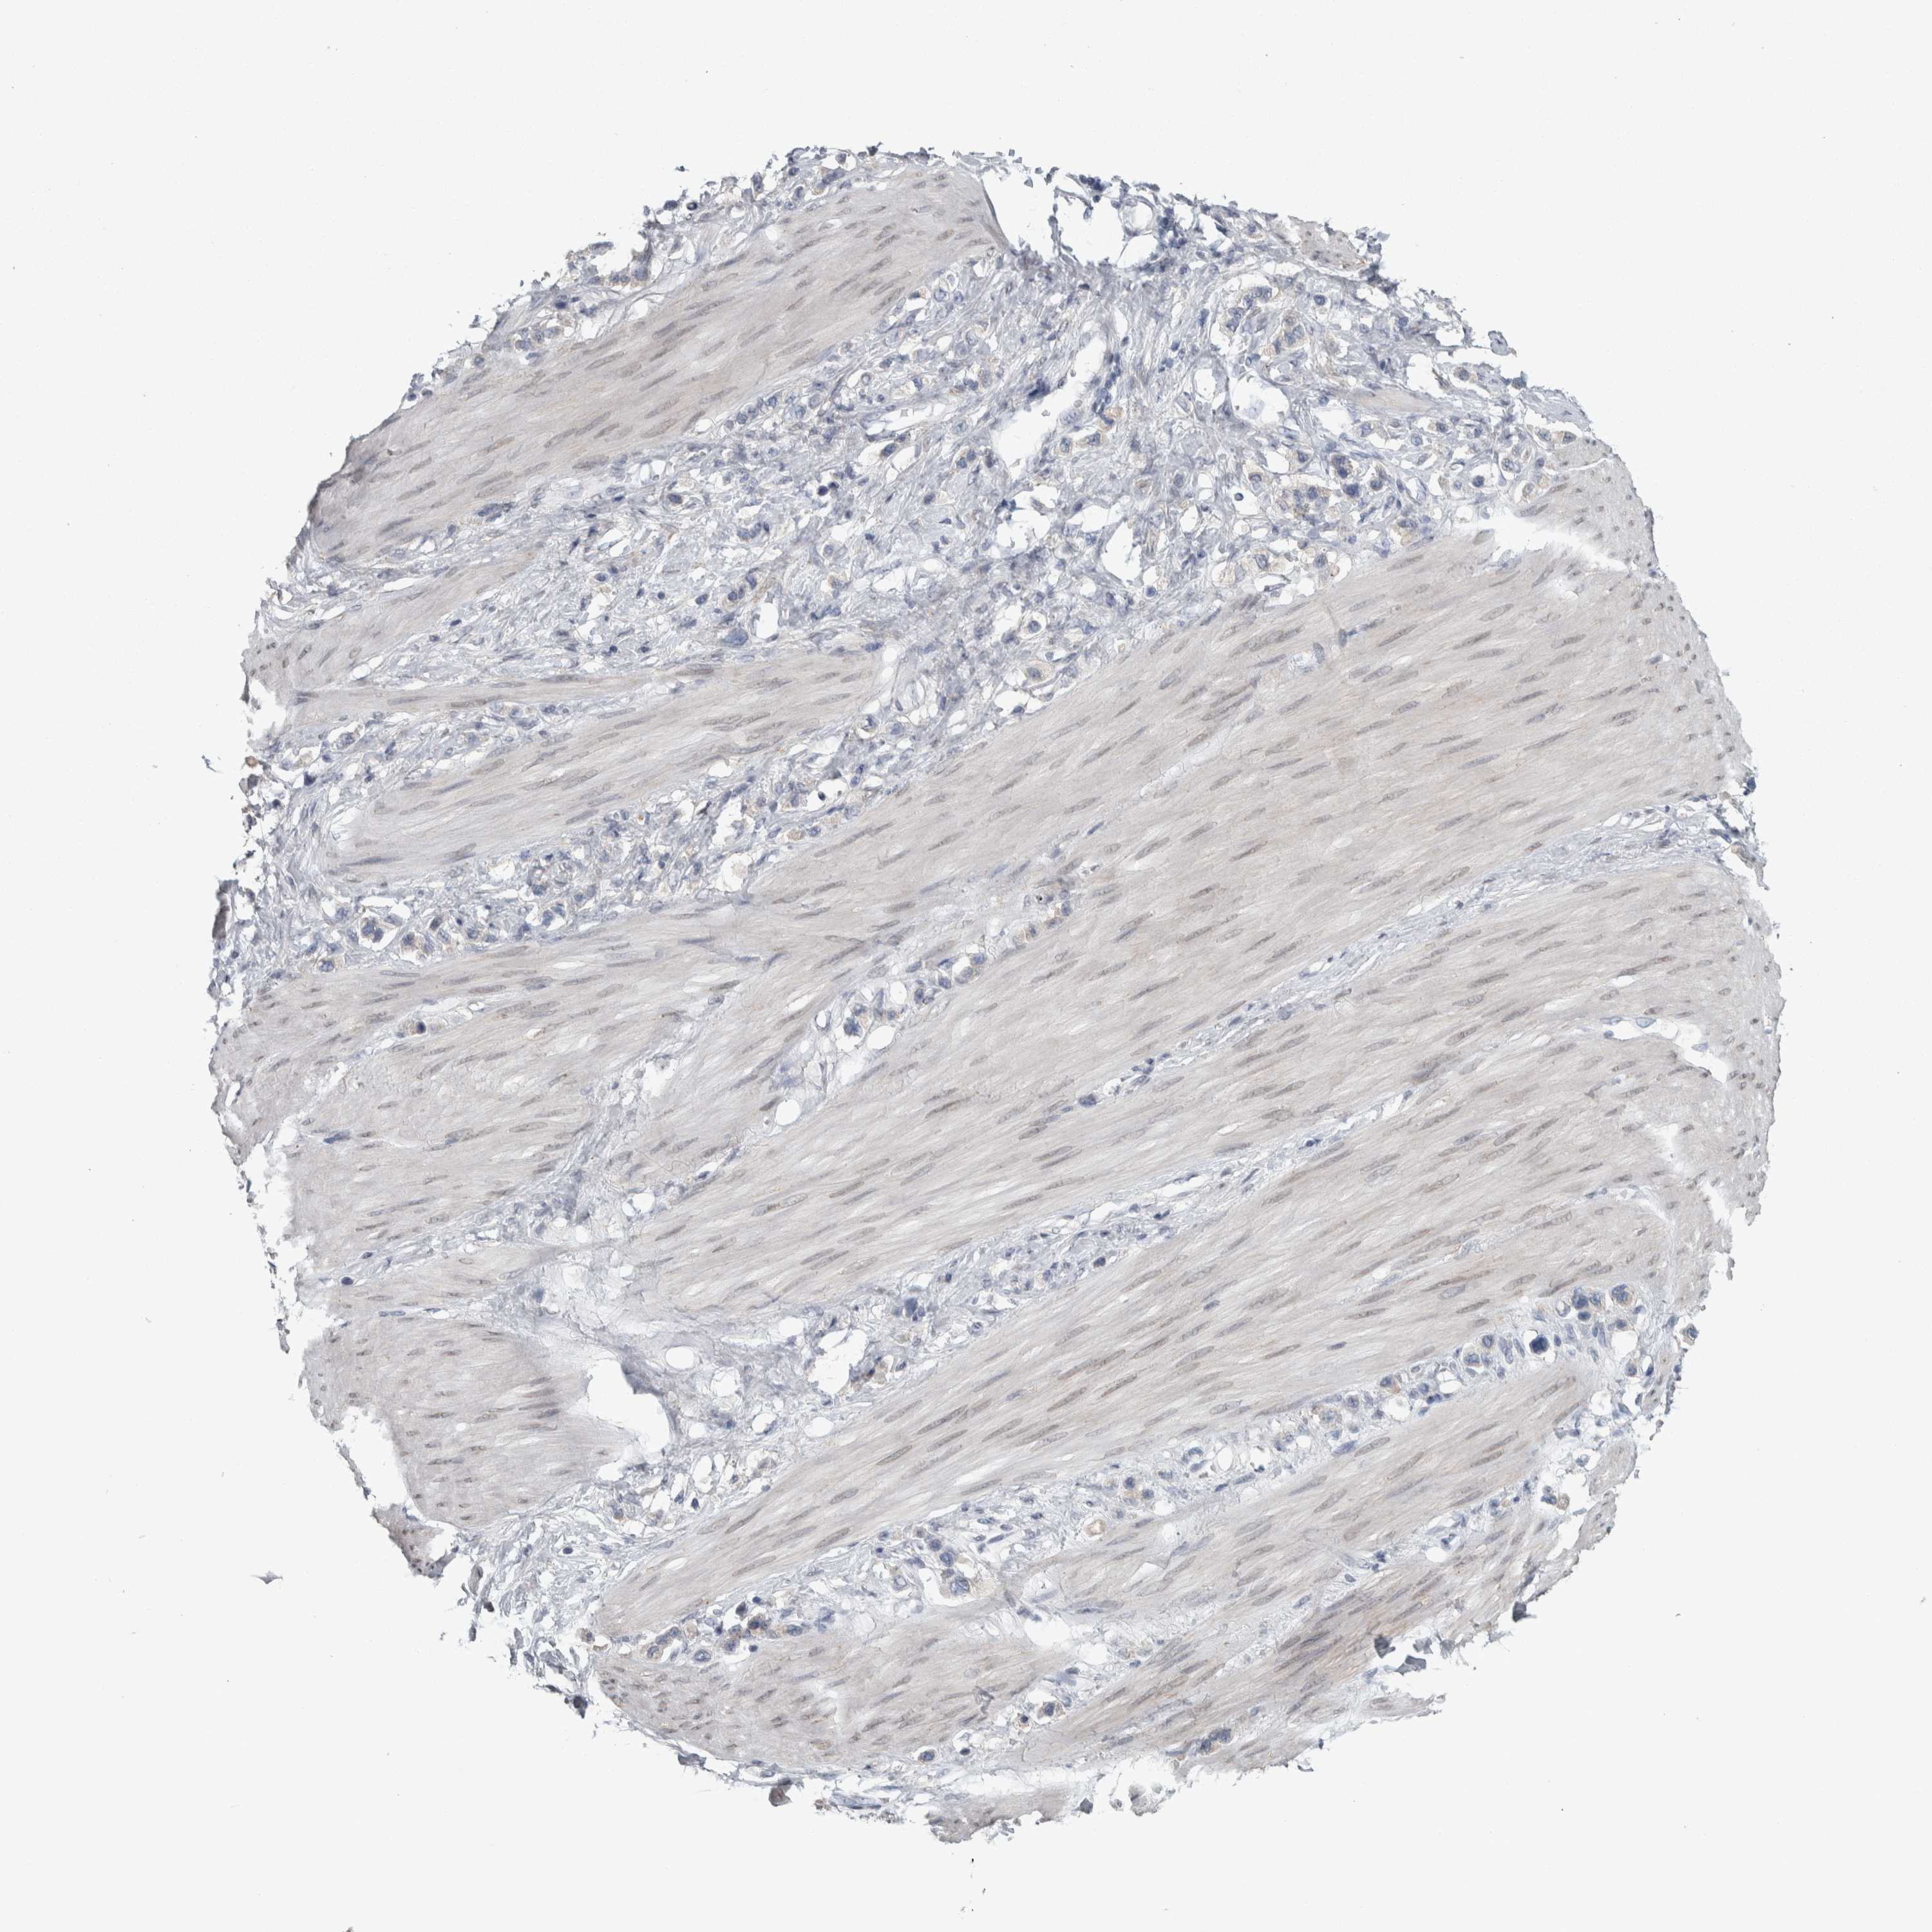

STOMACH CANCER - Protein expressioni

A mouse-over function shows sample information and annotation data. Click on an image to view it in a full screen mode. Samples can be filtered based on level of antibody staining by selecting one or several of the following categories: high, medium, low and not detected. The assay and annotation is described here.

Note that samples used for immunohistochemistry by the Human Protein Atlas do not correspond to samples in the TCGA dataset.

Antibody stainingi

Antibody staining in the annotated cell types in the current human tissue is reported as not detected, low, medium, or high, based on conventional immunohistochemistry profiling in selected tissues. This score is based on the combination of the staining intensity and fraction of stained cells.

Each image is clickable and will lead to virtual microscopy that enables deeper exploration of all samples and also displays staining intensity scores, fraction scores and subcellular localization as well as patient and tissue information for each sample.

Antibody HPA018002

Antibody HPA024071

Antibody CAB013470

Staining

High

Medium

Low

Not detected

Intensity

Strong

Moderate

Weak

Negative

Quantity

>75%

75%-25%

<25%

None

Location

Nuclear

Cytoplasmic/membranous

Cytoplasmic/membranous,nuclear

Adenocarcinoma, NOS

Adenocarcinoma, High grade